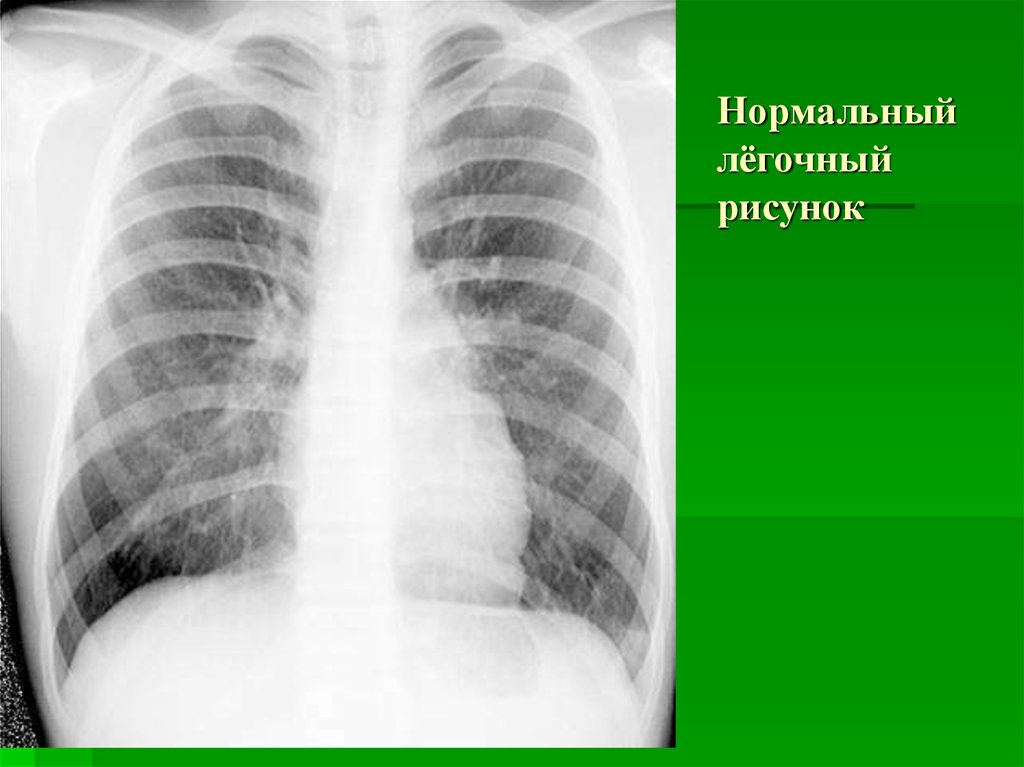

Ячеистая деформация легочного рисунка: медицинская визуализация